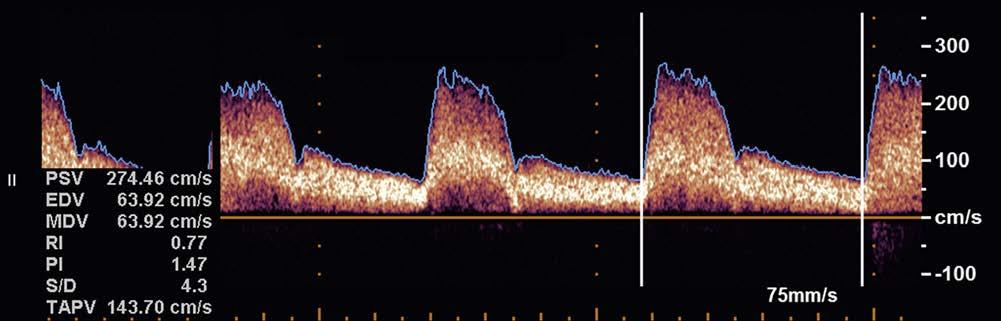

enable color-coded 2D and 3D presentations of Doppler information (color-Doppler displays) to be superimposed on gray-scale anatomic images (Figure 1-13). Doppler information is applied to loudspeakers for audible evaluation and to spectral-Doppler displays for quantitative analysis (Figure 1-14). The spectral-Doppler operation includes

anatomic imaging to determine the location(s) from which the spectral information is acquired (Figure 1-15).

FIGURE 1-14 Spectral-Doppler display of arterial blood flow with presentation of calculated flow velocity data.

FIGURE 1-15 Spectral-Doppler display of blood flow in the carotid artery. The anatomic image shows the location (arrow) from which the spectral-Doppler information was acquired.